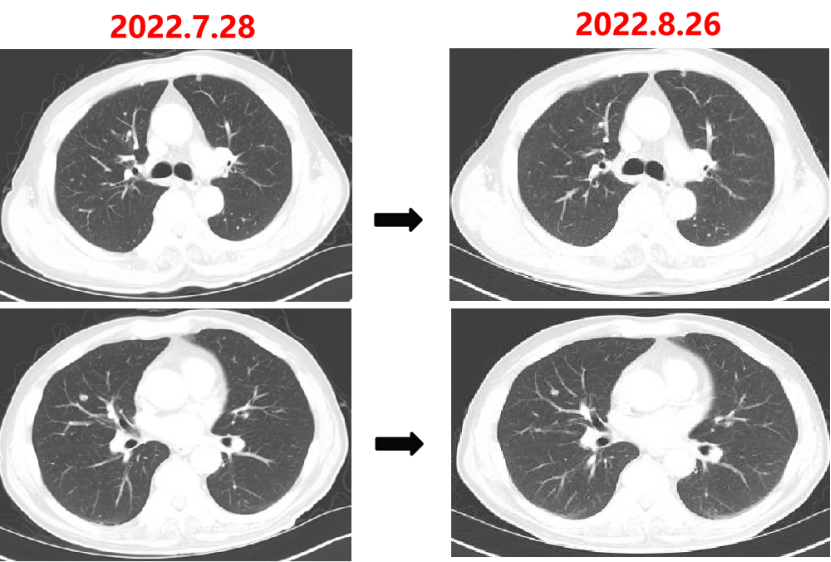

Q1 对于晚期转移性结直肠癌患者,目前,免疫治疗在新辅助治疗中的研究进展和临床应用如何? 结直肠癌是全球第三大肿瘤,转移性结直肠癌的5年生存率只有14%,治疗手段包括手术、化疗、放疗和靶向治疗等。免疫检查点抑制剂的出现也改写诊疗指南。大肠癌dMMR/MSI-H亚型约占所有病例的15%和mCRC病例的5%。由于dMMR/MSI-H的高突变率,肿瘤具有高免疫原性,使其能够激活免疫系统的抗肿瘤作用。 KEYNOTE-177这是一项三期国际开放标签随机对照研究,入选MSI-H/dMMR的IV期结直肠癌患者,比较帕博利珠单抗治疗(200 mg,每3周1次,最多35个周期)与在一线中使用或不使用抗VEGF或抗EGFR单克隆抗体的标准双药化疗,主要终点是PFS和OS。结果显示,帕博利珠单抗组患者的中位PFS时间为16.5个月 VS 8.2个月;3年PFS率分别为42% VS 11%,3年OS率分别为61% VS 50%。帕博利珠单抗组ORR为45.1%(20例完全缓解,49例部分缓解),化疗组为33.1%(6例完全缓解,45例部分缓解);帕博利珠单抗组83.5%的患者至少维持缓解了2年;在化疗组中,只有33.6%的患者缓解持续时间≥2年。KEYNOTE-177研究证实了帕博利珠单抗可以作为MSI-H或dMMR患者的一线标准治疗。 在2021版CSCO结直肠癌诊疗指南中,MSI-H结直肠癌姑息一至三线均推荐免疫治疗,其中帕博利珠单抗作为一线治疗的一级推荐;CheckMate-142研究选择MSI-H/dMMR转移性结直肠癌患者,单免后线vs双免后线vs 双免一线:ORR 39% vs 65% vs 71%,DCR 69% vs 81% vs 84%,一线双免完全缓解率为13%。结果说明双免好于单免,一线好于后线。CheckMate-142研究具有划时代意义,它将免疫治疗从后线前移到一线。 COMMIT研究是一项前瞻随机开放标签的三期临床研究,评估了阿特珠单抗单药治疗对比mFOLFOX6(氟尿嘧啶、奥沙利铂、亚叶酸钙)+贝伐珠单抗+阿特珠单抗一线治疗dMMR或MSI-H转移性结直肠癌的疗效和安全性,目前该试验还在进行中。未来该项研究的结果将回答对于MSI-H晚期结直肠癌,在一线免疫治疗的基础上联合化疗和抗血管靶向药物是否可以进一步提高免疫治疗的疗效。 CheckMate 8HW是另一项随机对照三期临床研究,在一线治疗dMMR或MSI-H转移性结直肠癌中,比较纳武利尤单抗单药、纳武利尤单抗联合伊匹木单抗以及研究者选择的化疗这3种方案的疗效。这项研究将头对头地比较对于MSI-H晚期结直肠癌双免联合是否优于单免的疗效。 Q2 对于MSI-H/dMMR型局部晚期结直肠癌(LACRC),新辅助免疫治疗探索的进展与应用前景如何?有哪些潜在预测疗效的生物标志物? 对于MSI-H/dMMR型局部晚期结直肠癌患者,新辅助免疫治疗可以在肿瘤手术前,提前使患者的免疫系统识别肿瘤细胞,从而使患者的免疫系统更好地产生免疫应答。目前结直肠癌新辅助治疗的探索均为二期研究,探索模式多为双免疫或免疫联合化疗方案,直肠癌多为免疫联合放化疗(同步或序贯)的模式。 NICHE研究是探索纳武利尤单抗联合伊匹木单抗用于Ⅰ-Ⅲ期结肠癌新辅助治疗的二期临床研究,研究共纳入40例结肠癌患者,其中21例为dMMR,20例为pMMR(1例患者同时为pMMR和dMMR),81%的dMMR患者和40%的pMMR患者为临床Ⅲ期结肠癌。患者在接受首次免疫治疗后不迟于6周内接受结肠癌手术,dMMR结肠癌缓解率100%,其中完全缓解的患者占60%,MPR为95%;pMMR治疗组27%的患者也对免疫治疗产生了良好的应答。 NICHE2研究,纳入更多患者,探寻非转移性dMMR结直肠癌患者双免治疗(伊匹木单抗+纳武利尤单抗)的疗效,主要终点为安全性,3年无病生存期。结果显示:MPR率95%,PCR率67%,中位随访13.1个月后没有患者出现疾病复发,毒性可耐受。 NCT04165772研究(前瞻性,单臂,Ⅱ期研究),Ⅱ期和Ⅲ期患者接受新辅助dostarlimab(多塔利单抗)共6个月,结果显示CCR率为100%。 PICC研究是特瑞普利单抗联合或不联合塞莱昔布新辅助治疗错配修复蛋白缺陷或微卫星高度不稳定的局部进展期结直肠癌的双臂随机Ⅱ期临床试验,结果显示完全缓解率高达88%,进一步表明dMMR结直肠癌免疫疗效惊人,潜在替代放化疗及手术。 对于MSI-H或dMMR结直肠癌,NCCN结直肠癌指南中,新辅助治疗增加纳武利尤单抗±伊匹木单抗或帕博利珠单抗单药方案;转化治疗可以选择双免疫或单免疫用药方案。 但并非所有患者都能从免疫治疗中获益,故筛选免疫治疗的疗效预测生物标志物将显得尤为重要。近年来研究主要集中在包括MSI-H、PD-L1过表达、TMB-H(TPS3645)、POLE或POLD1基因突变、PI3K/AKT/mTOR通路、新抗原(身份和数量)、免疫系统状态(免疫细胞特征、T细胞受体相关)等。 Q3 您如何看待对于临床中MSI-H/dMMR 转移性结直肠癌患者使用免疫治疗,部分患者仍然会出现耐药问题? Q4 晚期结直肠癌通常预后相对较差、患者生存期不长,依然是我国困扰结直肠肿瘤治疗的瓶颈问题,但有治愈的可能,此时临床医生制定正确合理用药方案尤为重要。今年上半年发布的CACA-RC指南推荐不适合强烈治疗患者应用曲氟尿苷替匹嘧啶片(TAS-102)联合贝伐珠单抗,作为晚期不可切除结直肠癌姑息一线治疗方案。请您谈谈该推荐治疗对我国晚期不可切除结直肠癌患者的临床治疗带来怎样的获益? 今年上半年CACA-RC指南推荐了不适合强烈治疗的患者应用TAS-102联合贝伐珠单抗作为不可切结直肠癌一线治疗方案,是在不可切除晚期结直肠癌一线治疗中石破天惊的一项突破。晚期mCRC的标准化疗方案在指南中是以奥沙利铂或伊立替康为基础的FOLFOX和FOLFIRI方案,在此基础上,可以根据基因分型联合西妥昔单抗或者贝伐珠单抗,但是依旧有部分患者身体状况无法耐受加强化疗,针对这一类患者的治疗方案选择非常有限,且预后情况并不理想。TAS-102+贝伐珠单抗治疗方案毒副反应相对较低,(临床试验提示比贝伐珠单抗联合卡培他滨效果好)疗效确切,在未来较长一段时间内,尤其是目前疫情肆虐,患者不方便住院治疗时,TAS-102可作为国内不适合强烈治疗的mCRC患者及老年患者的一线治疗优选方案,并为患者带来持续的、更优的生存获益。 二 病例分享 专家简介 王峰 教授 医学博士,副主任医师,硕士研究生导师 滨州医学院附属医院肿瘤科副主任 澳大利亚悉尼维斯迈医学中心访问学者 中华医学会放射肿瘤治疗学分会骨与软组织学组委员 中国临床肿瘤学会(CSCO)神经系统肿瘤专家委员会委员 山东省医师协会肿瘤精准医疗医师分会常务委员 山东省医师协会肿瘤放疗医师分会委员 山东省抗癌协会消化道肿瘤分会常务委员 山东省医学会咽喉肿瘤多学科联合委员会委员 山东省医学会烟草病学与戒烟多学科联合委员会委员 山东省健康管理协会消化道肿瘤防治分会常务委员 山东省医学会放射肿瘤学分会青年委员 山东省医学会妇科肿瘤多学科联合委员会委员 滨州市医学会放射肿瘤学专业委员会副主任委员 01 基本情况 (一)基本信息 患者男性,65岁,于2021-08-26第一次入滨州医学院附属医院风湿免疫科。 主诉:发作性右踝关节肿痛3年,再发1月。 查体:双足第一跖趾关节可见红肿,伴局部皮温升高。 既往史、个人史:既往脑梗死病史7年余,未遗留后遗症;有“膀胱结石”病史1年余,未系统诊治;有“痛风性关节炎”3年余,曾于滨州医学院附属医院风湿免疫科治疗。有高血压病史10年余,最高血压180/110mmHg,口服“吲达帕胺片”,血压控制可。 常规检查发现2次大便潜血阳性。 (二)辅助检查结果 1.肠镜检查 直肠、乙状结肠:直肠距肛门7cm可见一巨大溃疡型病变,表面溃烂,污秽苔,周边环堤样隆起,累及管腔1/3周圈,管腔无狭窄,于病变周边多点活检8块,质脆易出血;乙状结肠见一0.5cm*0.3cm息肉,余黏膜光滑,皱襞清晰,蠕动规律;肛管未见异常。降结肠、横结肠:横结肠见一0.3cm*0.4cm 0-IIa型息肉,表面粗糙,余黏膜光滑,血管纹理清晰,未见异常。 诊断:1.直肠Ca(进展期 溃疡型);2.结肠多发息肉——内镜下冷切除术+息肉摘除术。 2.胸部、上腹部未见明显异常。 直肠MR增强+DWI:直肠距肛缘约5.5cm处肠壁明显不均匀增厚,累及长度约6.0cm,呈等/长T1、等/稍长T2信号,T2压脂呈不均匀高信号,DWI呈高信号,ADC图信号减低,增强扫描呈明显不均匀强化,相应局部管腔狭窄,邻近浆膜面模糊,周缘可见小淋巴结。 02 治疗经过 2021-09-08:于全麻下行全直肠系膜切除+末端回肠预防造瘘术。 术中见:肝脏、胃、腹壁等无转移性结节。肿块位于腹膜返折处,活动度差,侵及浆膜。肠周见明显散在肿大淋巴结。 术后病理:直肠下段中分化腺癌,侵犯外膜下脂肪组织,肿瘤出芽分级(高级别,Bd3),侵犯神经侵犯,未见确切脉管内癌栓;两侧手术切缘、环周切缘及标记切缘内均未查见癌累及,肠周淋巴结内未查见转移癌(0/17)。pTNM分期:pT3N0Mx。免疫组化结果:CK(+),MSH2(+),MSH6(+),MLH1(+),PMS2(+),MDR-1(3+),HER2(3+),P53(3+),Ki-67阳性率约70%。 术后诊断: 1.直肠癌II(pT3NOMO)期术后; 2.结肠多发息肉术后; 3.痛风性关节炎; 4.高血压病(3级 很高危); 5.脑梗死。 CSCO指南: 2021-10-04至2022-06-03:FOLFOX方案化疗10周期(奥沙利铂150mg d1+氟尿嘧啶 0.7g d1+4.4g civ);术后预防性放射治疗DT5000cGy/25f,同步卡培他滨。 2021-11-25至2021-12-06:尿培养提示肺炎克雷伯菌感染,结合泌尿外科、感染科会诊意见,给予左氧氟沙星抗感染治疗。 2022-06-12 肺无法穿刺活检。 基因检测示:(直肠)KRAS/BRAF/NRAS/PIK3CA 基因均未检出突变。伊立替康UGT1A1基因检测结果:非风险基因型。 CSCO指南: 2022-06-20:西妥昔单抗联合FOLFIRI方案治疗(西妥昔单抗900mg d1,伊立替康320mg d1,氟尿嘧啶0.7g iv 4.3g civ)。 2022-07-06:骨髓抑制、腹泻,西妥昔单抗联合FOLFIRI方案治疗(西妥昔单抗900mg d1,伊立替康280mg d1,氟尿嘧啶0.7g iv 4.3g civ)。 疗效对比: 循证依据: C-TASK FORCE研究:首个证实TAS-102联合贝伐珠单抗治疗mCRC的疗效及安全性研究。TAS-102联合贝伐珠单抗是难治性mCRC患者潜在治疗选择,更多临床获益有待进一步研究。 TAS-102联合贝伐珠单抗治疗mPFS时间和mOS时间分别为5.6个月和11.2个月。 TAS-102联合贝伐珠单抗不良反应主要为血液学毒性。 日本大样本RWS:TAS-102和瑞戈非尼不同排序的回顾性研究。 日本大样本RWS:TAS-102单药较瑞戈非尼单药,可显著延长mOS,降低AE。 日本大样本RWS:两药序贯疗效优于单药,且≥65岁先用TAS-102获益更显著。 日本大样本RWS:TAS-102序贯瑞戈非尼组持续治疗时间更长。 2022-07-27至今 给予贝伐珠单抗联合TAS-102治疗期间复查CT评估SD,胃肠道反应不重,骨髓抑制Ⅰ度,耐受性尚可。 *本文仅代表专家观点,并经专家审校。